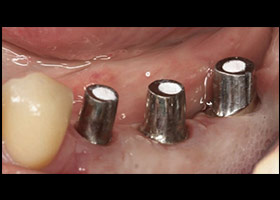

proimages/case/Artificial_implant/Horny4.jpg

順利植入植體